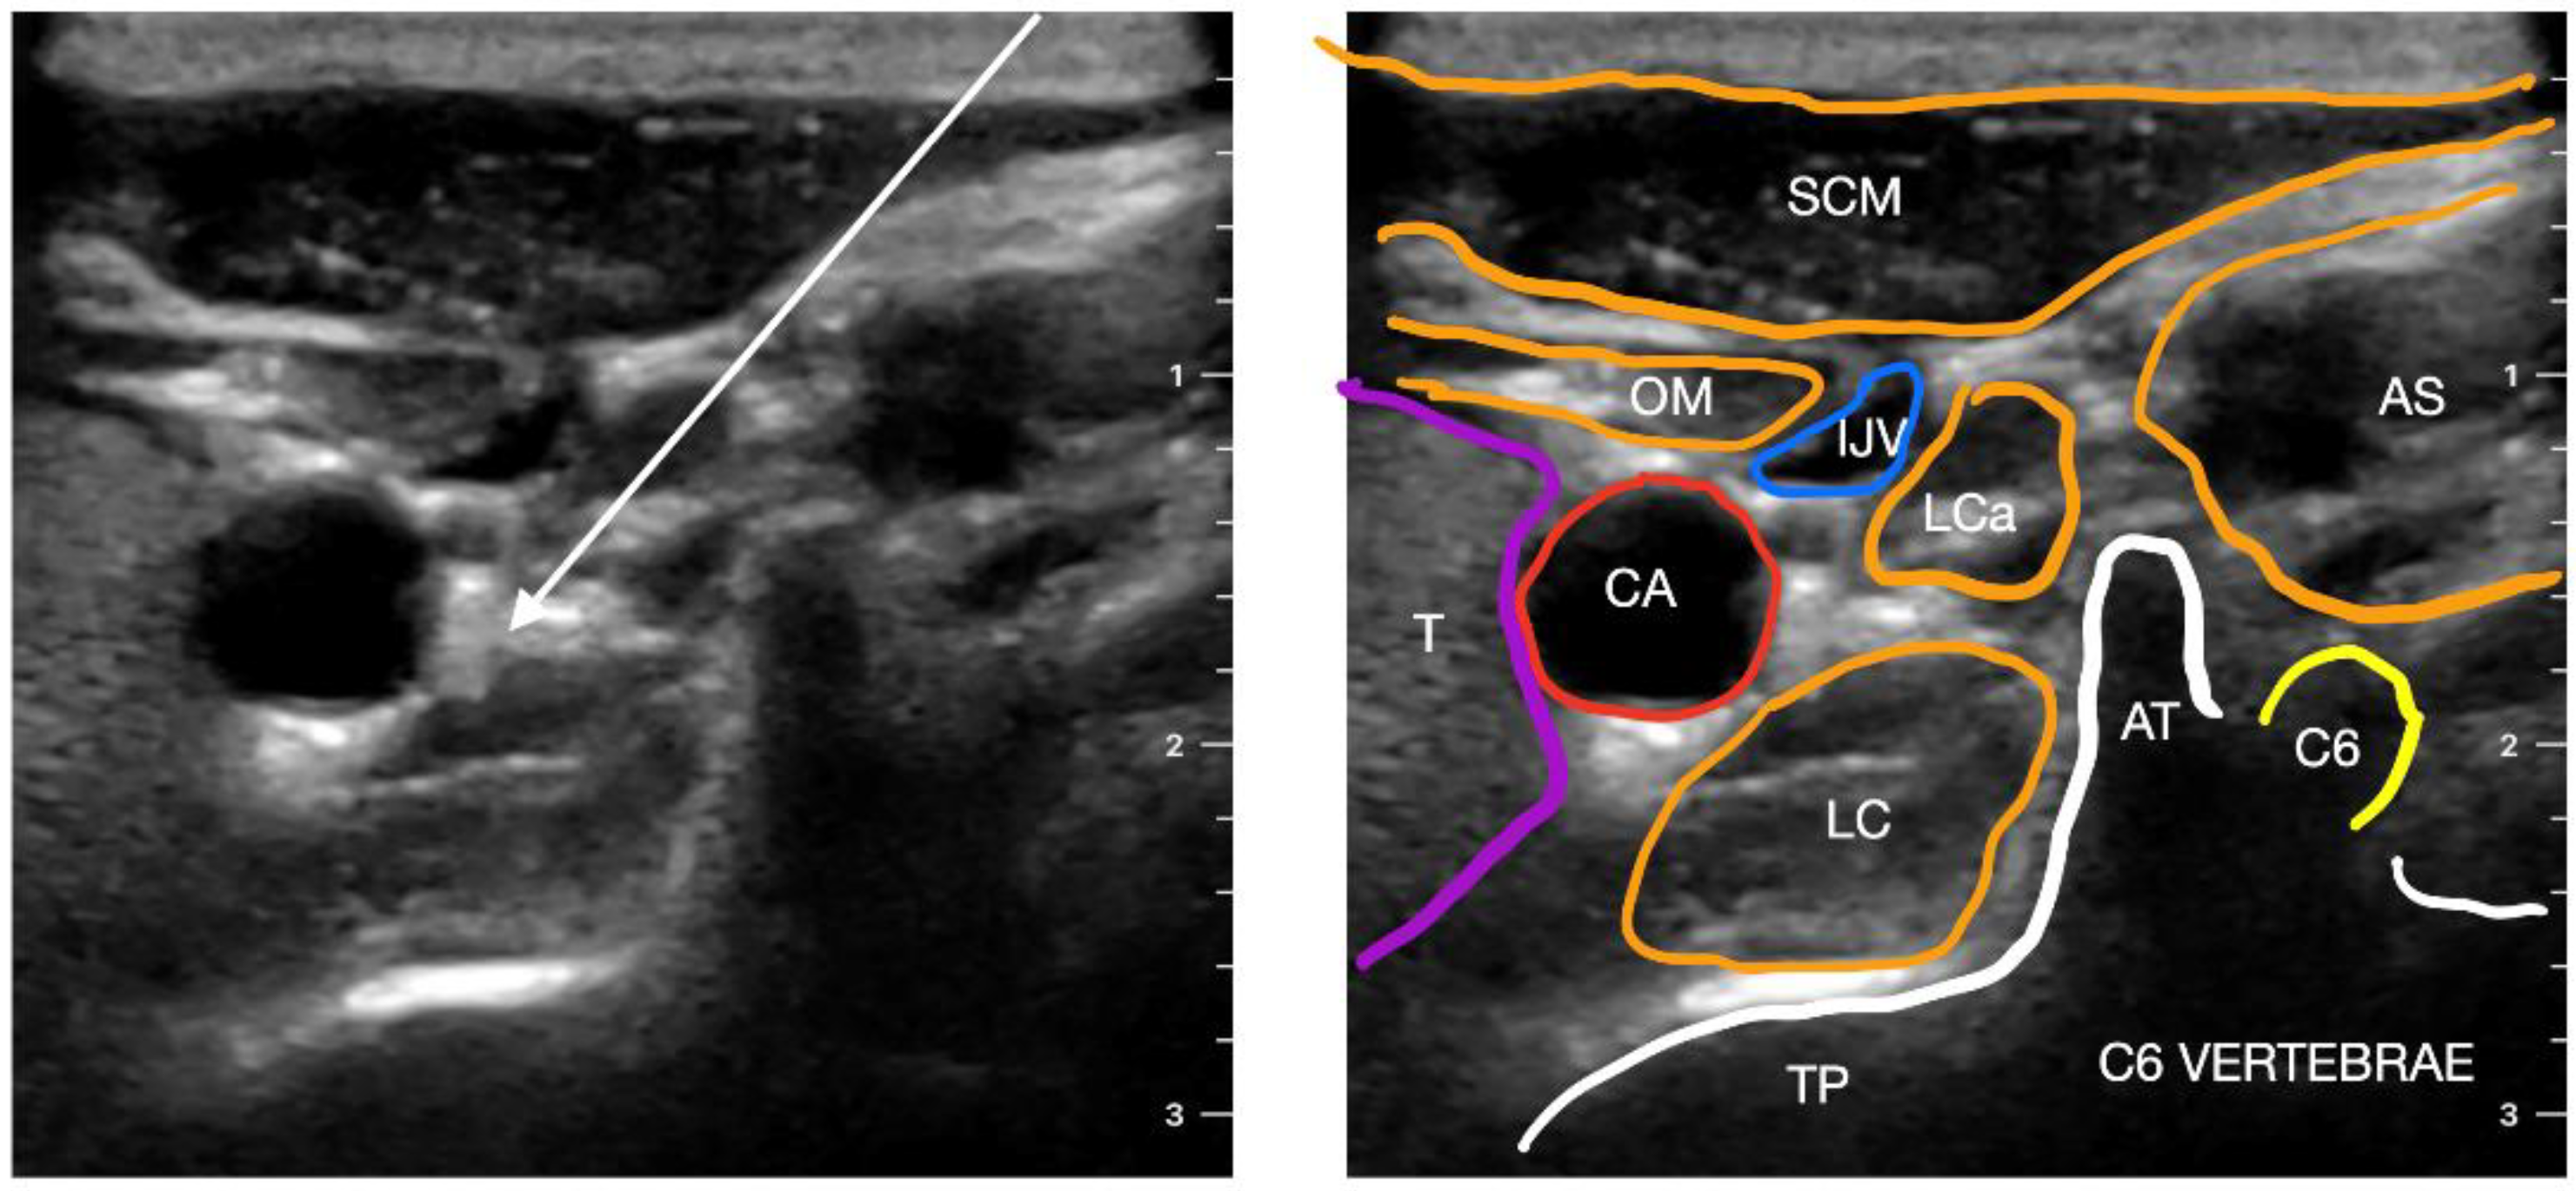

7. Stellate Ganglion Block